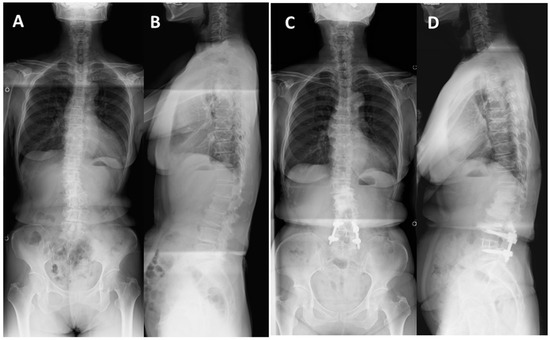

Case Presentations